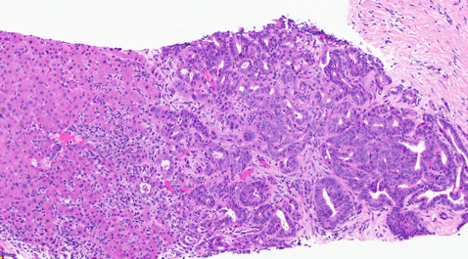

The patient is a middle-aged female with elevated liver enzymes. CT abdomen demonstrated multiple liver lesions with the largest mass measuring 7 cm. There is no primary neoplastic abnormality identified within the abdomen. She underwent a core needle biopsy of her liver lesion. Microscopic examination confirmed a moderately differentiated adenocarcinoma which was clinically consistent with an intrahepatic cholangiocarcinoma (Figure 1). A formalin-fixed, paraffin embedded tissue block of the core needle biopsy was sent for next generation sequencing (NGS) and an oncogenic NRG1 gene fusion was detected. Finally, the patient was started on targeted drug therapy with Seribantumab.

Figure 1: H&E Image of the Liver Lesion Biopsy